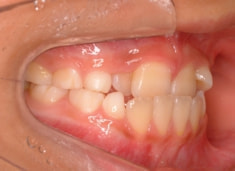

治療前

しかしやはり上顎は劣成長で、下顎が優位な状態ではあります。

検査時のレントゲン分析では、上下顎の関係は、上顎の劣成長があり下顎前突傾向という値がでておりましたが、前歯ジャンプ後はフェイスマスクの効果もあり、上下顎の関係は正常化しています。